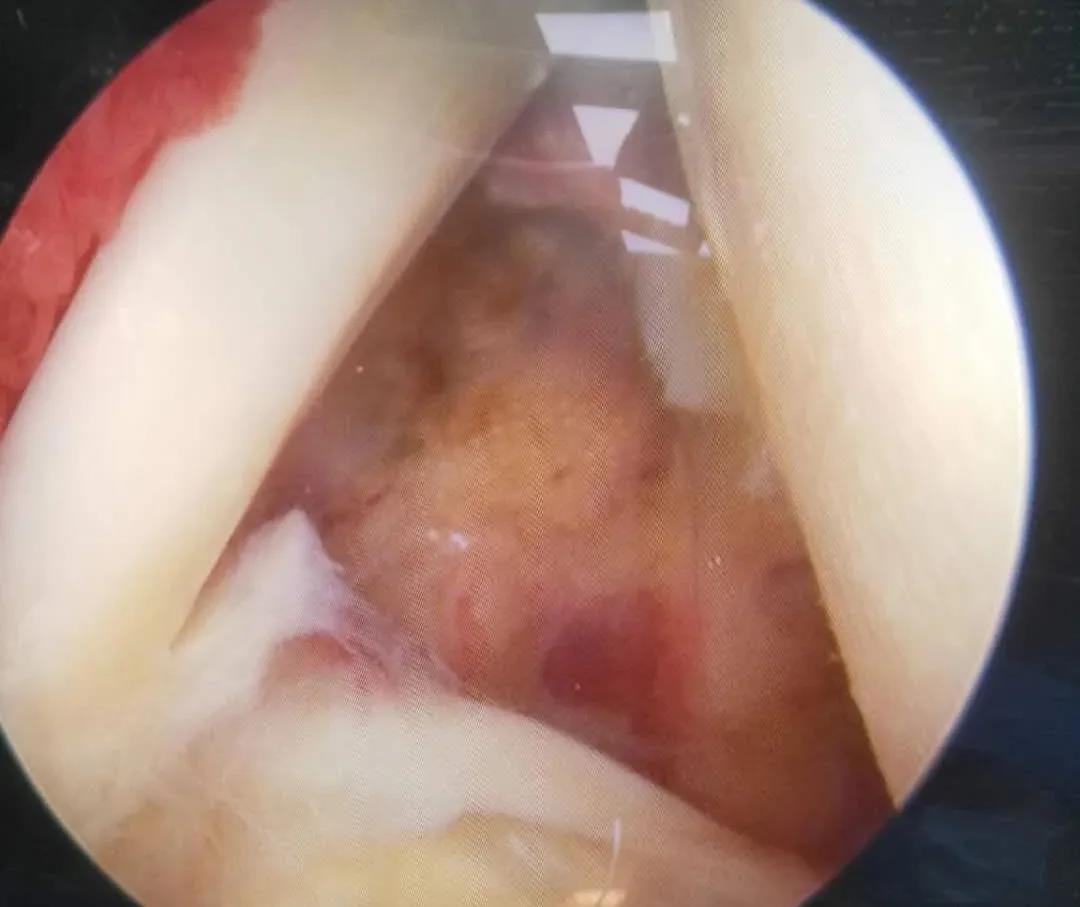

成人股骨頭無菌性壞死為成人常見髖關節(jié)疾病,導致髖關節(jié)周圍疼痛,最終導致患者行走困難,骨二科根據患者患者股骨頭壞死的ARCO分期,早期采用髖關節(jié)鏡加自體打壓植骨并PRP治療,能夠使股骨頭壞死區(qū)域血管再通,恢復髖關節(jié)的功能,避免最終的髖關節(jié)置換。

保髖治療